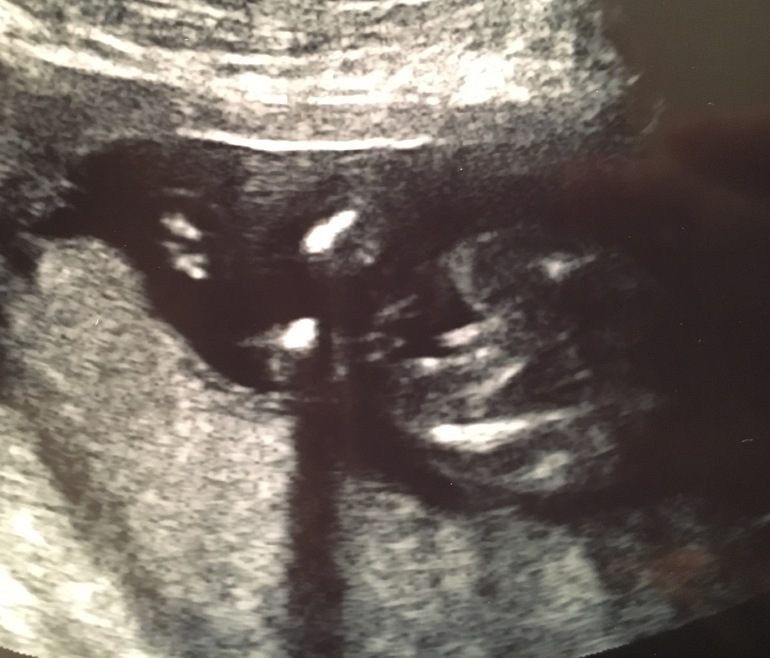

Девочка или мальчик ? 16 недель

мне кажется,что там вообще ничего не видно. Ножки скрестил и все. А то что торчит,пуповина.

У меня в 16 недель и у девочки вот так торчало, но это не пиписки была. На этой фотографии точно плохо видно

Тут плохо видно. Непонятно кто.

Меня смущает , что не очень похож на парня, пересмотрела фотограф парней нашего срока, там яички выраженные, а у нас их нет ... и будто что то пополам поделено

Коки и писюн торчит, вам чёт не нравится, половинки какие-то видите. Именно так все у мальчиков пока припухлое.

Да в том то и дело что с девочкой у меня такое же фото имеется )

В профиль не смотрели , это и смущает . Сверху не очень похож на парня, пересмотрела фотограф парней нашего срока, там яички выраженные, а у нас их нет ... и будто что то пополам поделено